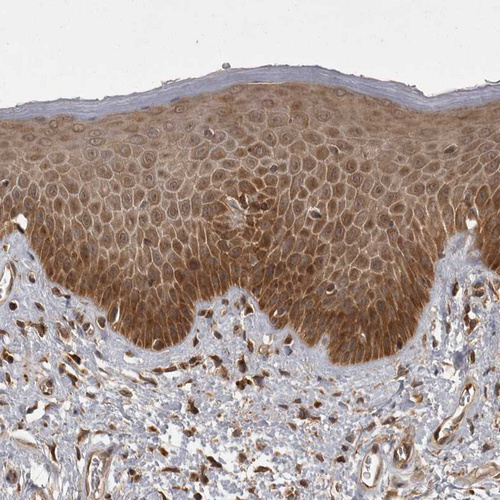

Immunohistochemical staining of human liver, skin, small intestine and testis using Anti-STK24 antibody HPA026435 (A) shows similar protein distribution across tissues to independent antibody HPA026502 (B).